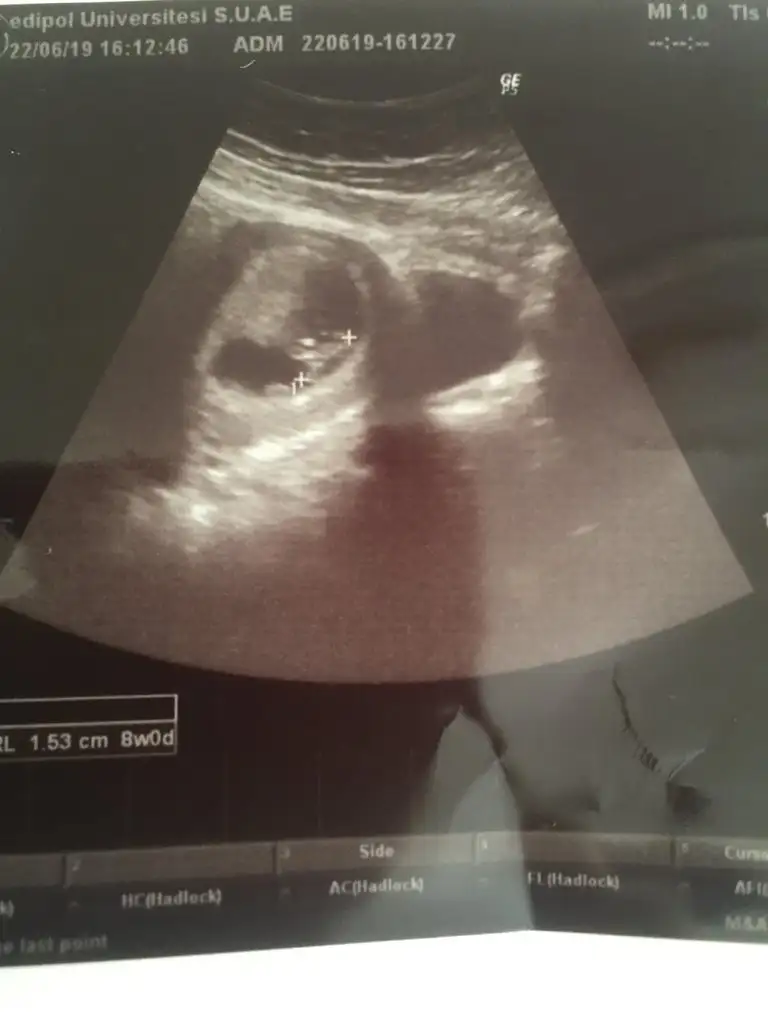

İlk 2 foto karından 8+3 , son 2 foto ise alttan 6+6

6+6 vajinal ise kız karından ise erkek 12 hafta nub teorisine paylaşırsınızİlk 2 foto karından 8+3 , son 2 foto ise alttan 6+6

Buda benim ki kız diye tahmin edildi erkek çıktıEki Görüntüle 2277369 Acaba benim bebişimin Cinsiyeti ne olabilir 8 haftalık Karından

Teori %85 dogrulugu varmış ama 7 hafta olmalı bu teori için usg sizinkilerr 10+3 ve 8 hafta bu teori için uygun degillermişBuda benim ki kız diye tahmin edildi erkek çıktı